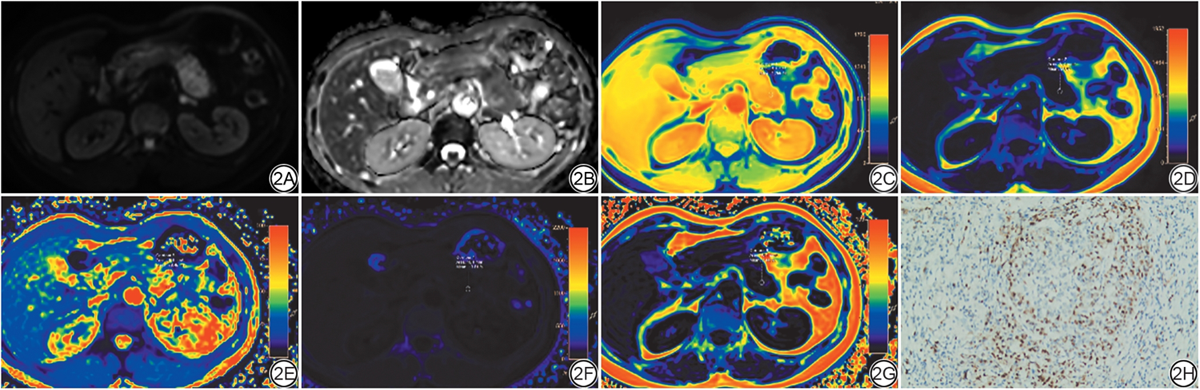

图2  女,46岁,病理证实为低分化胰腺导管腺癌。2A~2G:分别为DWI(b=800 s/mm2)、ADC、水相、脂相、T2*相、R2*相及FF图,其ROI水相值、脂相值、T2*、R2*及FF分别为:1 255.46、56.57、78.45 ms、13.81 s-1、2.44%;2H:Ki-67免疫组化(×100)示Ki-67高表达,Ki-67表达约70%。DWI:扩散加权成像;ADC:表观扩散系数;FF:脂肪分数;ROI:感兴趣区。

Fig. 2  A 46-year-old female patient with pathologically confirmed poorly differentiated pancreatic ductal adenocarcinoma. 2A-2G: DWI map (b = 800 s/mm2), ADC map, Water map, Fat map, T2* map, R2* map and FF map, respectively, the values of ROI are as follows: water value of 1 255.46, fat value of 56.57, T2* value of 78.45 ms, R2* value of 13.81 s-1, and FF value of 2.44%; 2H: Ki-67 immunohistochemistry (× 100) show high Ki-67 expression, with approximately 70%. DWI: diffusion-weighted imaging; ADC: apparent diffusion coefficient; FF: fat fraction; ROI: region of interest.